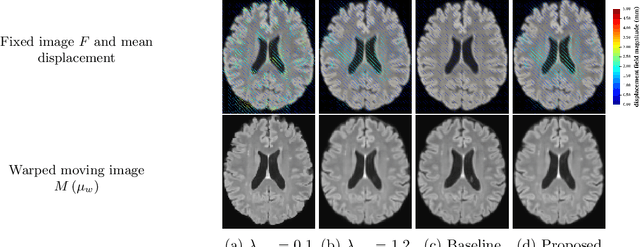

Abstract:We develop a new Bayesian model for non-rigid registration of three-dimensional medical images, with a focus on uncertainty quantification. Probabilistic registration of large images with calibrated uncertainty estimates is difficult for both computational and modelling reasons. To address the computational issues, we explore connections between the Markov chain Monte Carlo by backpropagation and the variational inference by backpropagation frameworks, in order to efficiently draw samples from the posterior distribution of transformation parameters. To address the modelling issues, we formulate a Bayesian model for image registration that overcomes the existing barriers when using a dense, high-dimensional, and diffeomorphic transformation parametrisation. This results in improved calibration of uncertainty estimates. We compare the model in terms of both image registration accuracy and uncertainty quantification to VoxelMorph, a state-of-the-art image registration model based on deep learning.